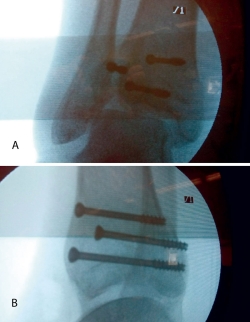

2. Fractura espiroidea con afectación articular, reducida mediante medios externos bajo control radioscópico y fijada con tornillos percutáneos.

Bajo anestesia raquídea e isquemia en la raíz del miembro afecto, colocamos al paciente en decúbito supino con la pierna en férula de Braun y una tracción en el tobillo con vendas o con sistema de tracción suministrado por casas comerciales.

Realizamos los portales artroscópicos habituales en función de la situación de los extremos óseos de la fractura y practicamos un procedimiento idéntico al anterior: lavado, desbridamiento e identificación del foco de fractura (Figuras 12 a 16).

Figura 12. Caso 2: fractura espiroidea con afectación articular. Posicionamiento en férula de Braun. Tracción con vendas. Realización de portales.

Figura 13. Posteriormente, realizamos la limpieza del foco con cucharilla y la reducción del mismo mediante pinzas de cóndilo bajo control radioscópico/artroscópico, y fijación provisional con agujas de Kirschner.

Figura 14. A continuación, se realiza la medición y colocación secuencial de los tornillos.

Figura 15. Por último, se procede a la colocación definitiva de los tornillos.

Figura 16. Resultado final a los 4 meses.